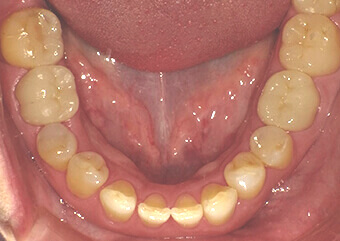

被せ物 施術後

奥歯の金属のかぶせ物、詰め物をセラミックスで再修復しました。セラミックスは欠けやすい(壊れやすい)と言われたのは昔の話で、噛む力にも耐えうる十分な強度を持ち合わせています。周りの色調に合わせるための色付けを省いて作製することで、コストを抑えることもできます。